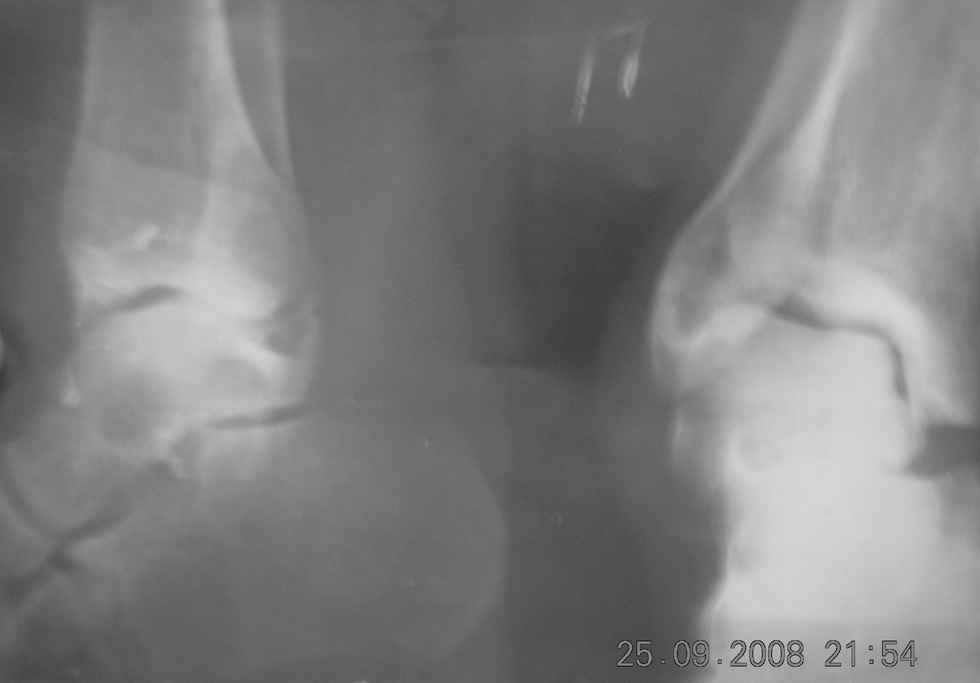

Bolnoy tri mesatsa tomu nazad padvernul nogu lechilsya v SRB

nalojen gips, snyat cherez tri mesatsa posle snyatiy gipsa

atmechayetsya varusnaya defarmatsiya stapi boli pri nagruzke

konechnosti prashu pomoch v plane i taktiki lecheniya.